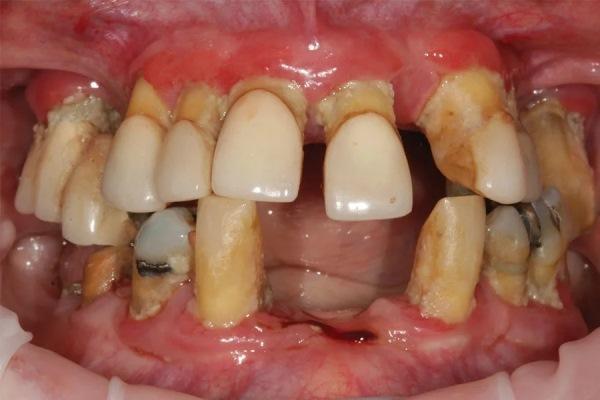

В апреле 2017 года 74-летняя пациентка обратилась с жалобой на то, что «все шатается» (Фото 1 и Фото 2). В анамнезе — гипертония и лечение рака груди в 2002 году с удалением левой молочной железы, но противопоказаний к стоматологическому лечению не было. Пациентка принимала Avapro и Pravachol и имела аллергию на пенициллин.

Фото 1: Клинический случай 1. Состояние пациентки при обращении.